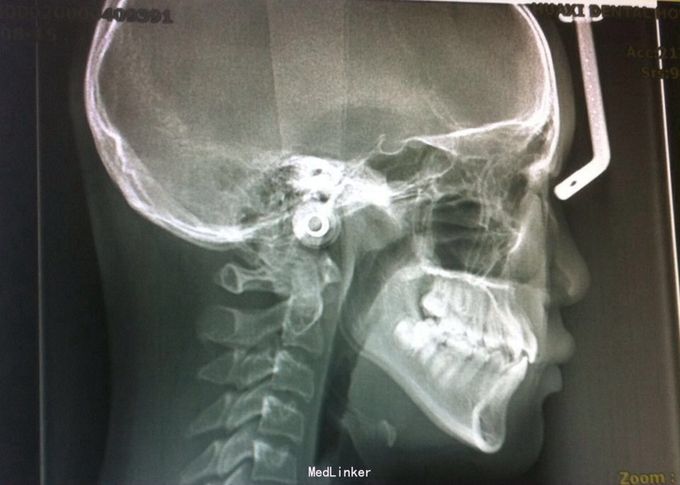

后牙反合 安氏三类

女 18y 主诉:牙齿不齐

恒牙期 左右磨牙近中关系 12,22舌侧错位 32、33融合牙 右侧磨牙反合 上下牙列轻度拥挤 关节有弹响

安氏三类、后牙反合 不拔牙矫治,直丝弓矫治器,排齐整平上下牙列,解除后牙反合,矫治后覆合覆盖正常,磨牙中性关系,维持现有面型